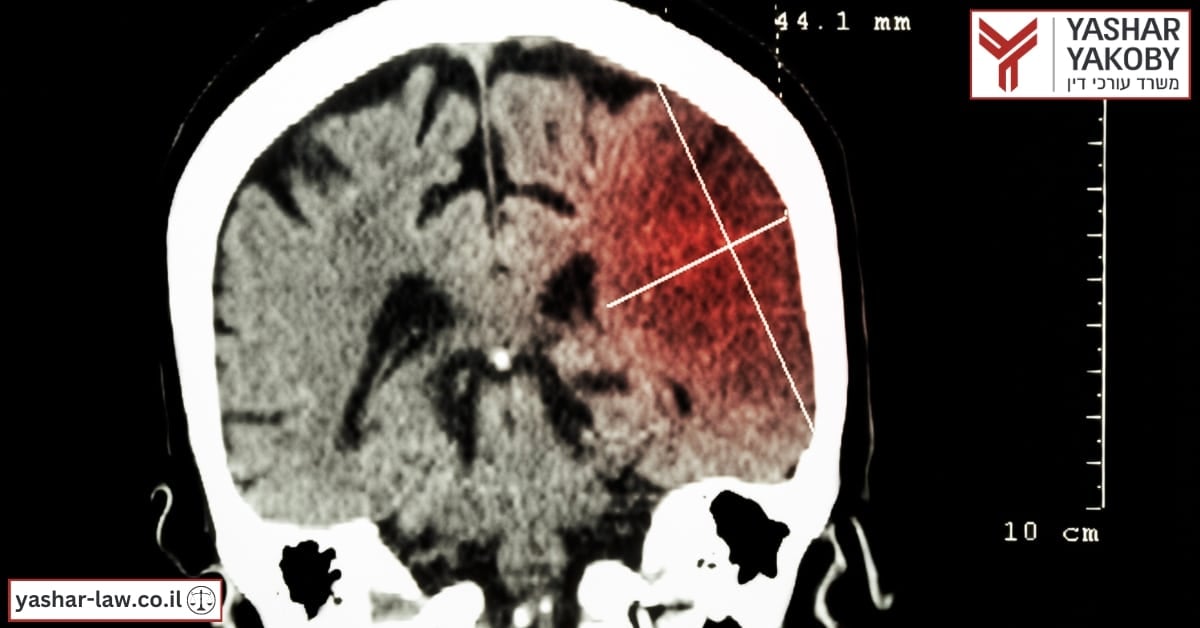

احتشاء الدماغ هو السبب الرئيسي للوفاة في سن الشيخوخة. يحدث احتشاء الدماغ بسبب جلطة دموية تسد الأوعية الدموية وتتسبب في موت خلايا الدماغ في منطقة الانسداد. ينقسم الخطأ الطبي فيما يتعلق باحتشاء الدماغ المؤدي إلى الشلل إلى نوعين من الخطأ. الخطأ الأول هو عدم العلاج الذي يؤدي إلى تكون جلطات الدم، والخطأ الثاني هو عدم التشخيص في الوقت المناسب لأن الشخص يكون في حالة احتشاء دماغي حتى يحدث ضرر لا رجعة فيه بما في ذلك الشلل. سنشرح في هذا المقال ما هو الخطأ الطبي فيما يتعلق باحتشاء الدماغ الذي أدى إلى الشلل وما يمكن فعله حيال ذلك.

الاحتشاء الدماغي هو حالة تقوم فيها جلطة دموية بسد الأوعية الدموية التي تغذي خلايا الدماغ. قد تكون هناك حالة من الانسداد الجزئي تؤدي إلى إبطاء معدل الدم وتجويع الخلايا، أو حالة شديدة من الانسداد الكامل تؤدي إلى موت الخلايا بشكل شبه فوري (في غضون أربع إلى ست دقائق) وتؤدي في الواقع إلى السكتة الدماغية. يمكن أن تكون السكتة الدماغية خفيفة وتتجلى في الصداع، والدوخة، وفقدان التوجه والارتباك، ويمكن أيضًا أن تكون شديدة مسببة نزيف داخل المخ، وفقدان الوعي، والشلل، والغيبوبة، والموت. يمكن الوقاية من السكتة الدماغية عن طريق منع أسباب جلطات الدم، مثل: إعطاء أدوية تسييل الدم والحفاظ على نمط حياة صحي. أمراض مثل: مرض السكري وارتفاع ضغط الدم وأمراض القلب وبعض الأمراض الوراثية يمكن أن تكون عوامل خطر للسكتة الدماغية. إذا وقع الشخص في حالة احتشاء دماغي، فإن علاماته هي في الواقع علامات السكتة الدماغية التي سببها، لذلك يجب الحذر والتفاعل فور ظهور العلامات النموذجية الأولى.

3.لماذا يمكن أن يؤدي احتشاء الدماغ إلى إصابة الشخص بالشلل؟

الاحتشاء الدماغي هو حالة تتوقف فيها خلايا الدماغ عن تلقي إمدادات الأكسجين بسبب انسداد الأوعية الدموية بسبب جلطة دموية. في هذه الحالة، ما بين أربع إلى ست دقائق كافية لإحداث ضرر لا يمكن إصلاحه لخلايا دماغ الشخص. في هذه الحالة، سيتعرض الشخص لسكتة دماغية، والتي قد تكون شديدة أيضًا وتسبب نزيفًا دماغيًا واسع النطاق. ومن النتائج المحزنة لسكتة دماغية حادة حدوث ضرر لا يمكن إصلاحه في أجزاء مختلفة من دماغه مما أدى إلى إصابته بالشلل في نصف جسده.